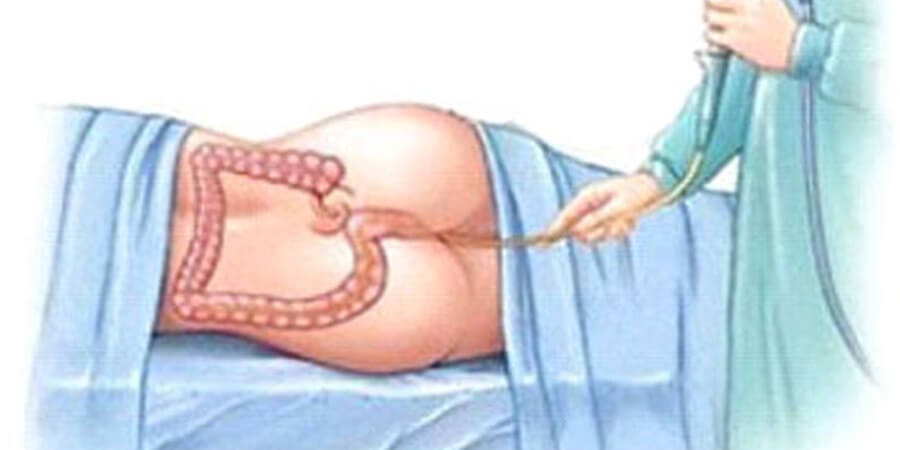

Detox Before Festive Season: Ayurvedic Panchakarma Timings That Work

Detoxifying with Ayurvedic Panchakarma is ideal two to three weeks before festive events. This timing allows for gradual dietary reintroduction and aligns with the lunar cycle, enhancing energy. Key treatments such as Abhyanga, Virechana and Basti support internal cleansing and rejuvenation. To prepare, individuals should maintain a balanced diet and gentle exercise. Post-cleanse, continuing hydration […]